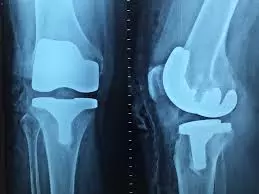

Ukvarjamo se z zdravljenjem težav s področja ortopedije, kot so težave s koleni, ramo, zapestjem, hrbtenico in podobno. Izdelujemo izvedeniška mnenja in sodelujemo pri raziskavah na tem področju. Dodatno v naši ponudbi najdete tudi prodajo ortopedskih pripomočkov.